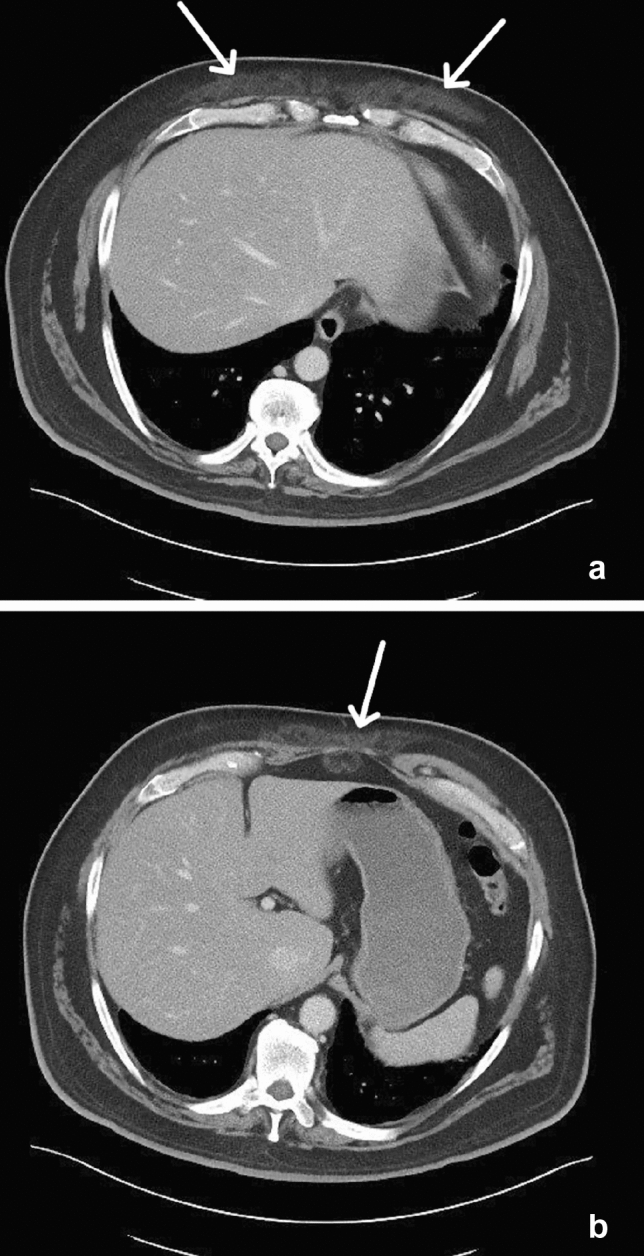

Fig. 1.

43-year-old male with bilateral pectineal muscle myonecrosis. Axial (a) and coronal (b) CT images of the abdomen and pelvis demonstrate ill-defined muscle enlargement and decreased attenuation of bilateral anteromedial compartments of the upper thighs (arrows). Axial (c) and coronal (d) T1W fat-saturated post-contrast MR images demonstrate bilateral peripheral enhancement (arrowheads) of the pectineus muscles surrounding central non-enhancing (arrows) muscle fibers representing myonecrosis